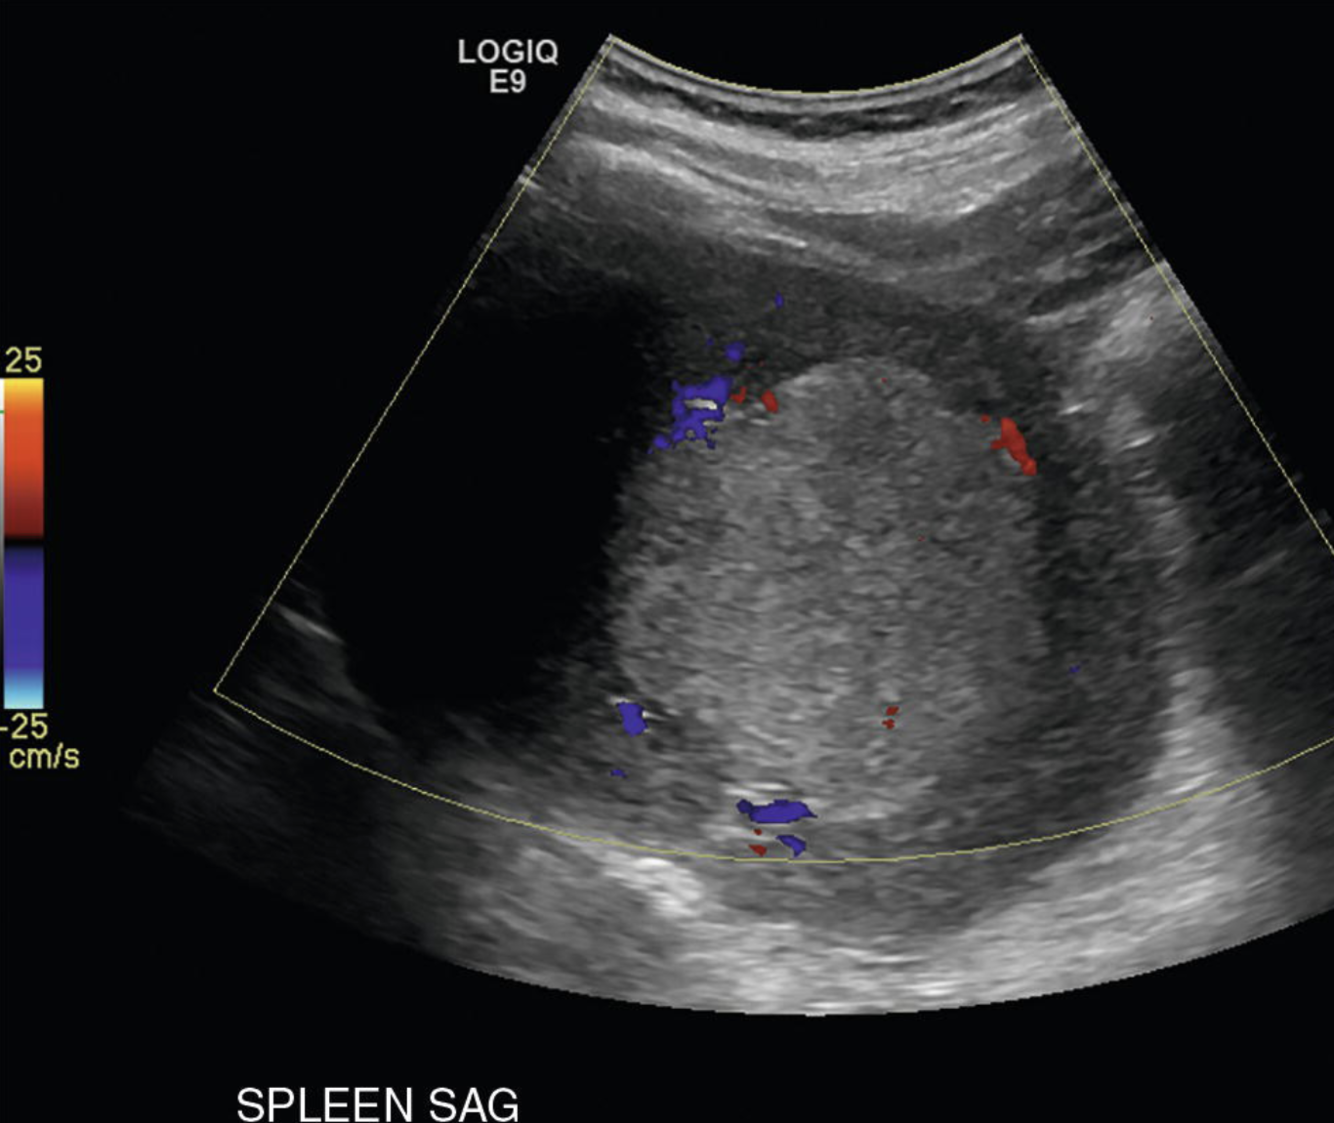

These splenic findings are most commonly associated w/what process?

Gamna-Gandy bodies = PHTN.